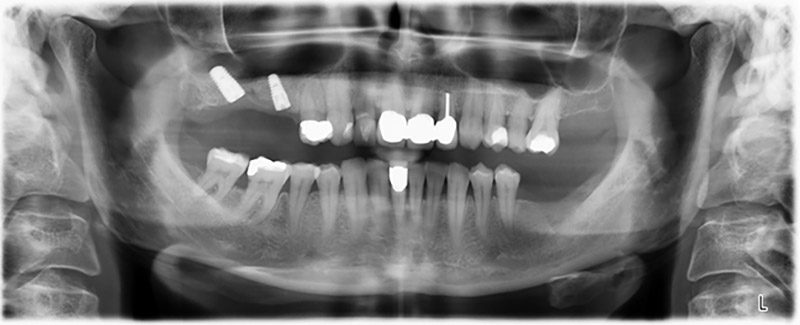

59-годишна пациентка с напреднал стадий на пародонтит описва неприятно чувство и лош вкус в първи квадрант в дисталната зона. Клиничният преглед разкрива силно уголемени пародонтални джобове и напреднала костна атрофия в зона 16 и 14. Рентгенографията потвърждава констатациите (Фиг. 1). Зъби 16 и 14 не могат да бъдат запазени.